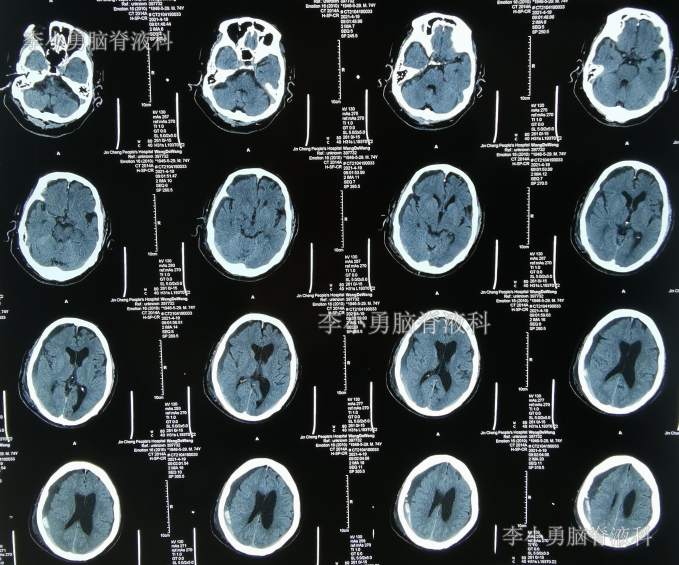

2021年4月17日(腰大池腹腔分流术后20天,硬膜下血肿引流术第1天),查头部CT示引流术后状态,仍有血肿(图-5)。

图-5:2021年4月17日头部CT

2021年4月19日(腰大池腹腔分流术后22天,硬膜下血肿引流术第3天),期间体位性头晕头痛、间断游走性腹痛也缓解,查头部CT示硬膜下血肿减少(图-6);给予拔除脑室外引流管。

图-6:2021年4月19日头部CT